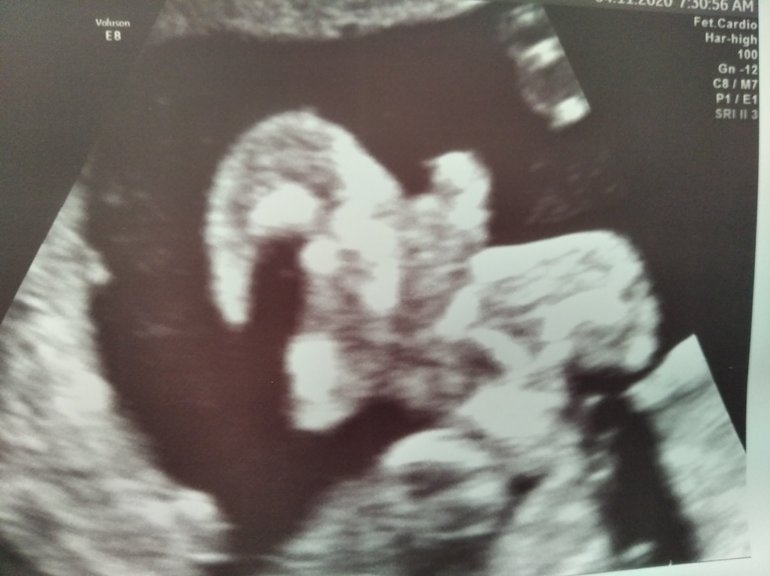

Вот на таком же сроке мой сын.

на кого похоже?